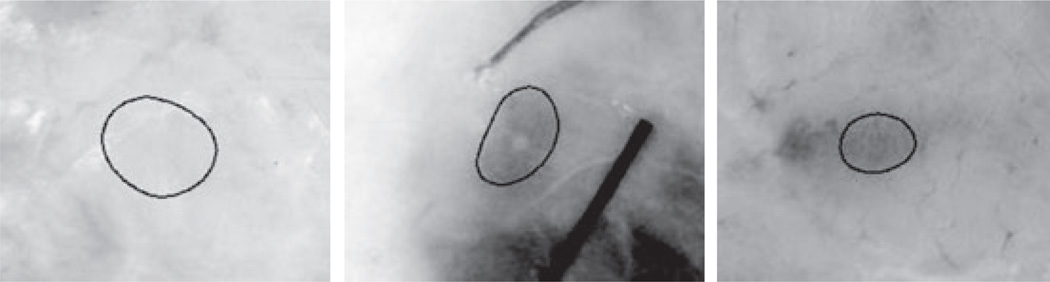

These objects are the dermoscopic equivalent of the clusters of pigmented basal cell tumor islands, which are the histopathologic hallmark of this skin malignancy (4). Because of the variation in color and size of these objects, B-GOs can be mimicked by any structure lying deeper in the skin (Fig. 2), creating a challenge for automatic detection of these structures. This article focuses on semi-automatic discrimination of these structures from mimics, using sector-based structure expansion and statistical modeling by logistic regression. The remainder of this article includes II. Materials and Methods, III. Experiments and Results, and IV. Discussion.

Fig. 2.

Examples of similar blue-gray structures found in various benign lesions. Note that hue, brightness, shape, size and indistinct borders can resemble those same features in blue-gray ovoids.